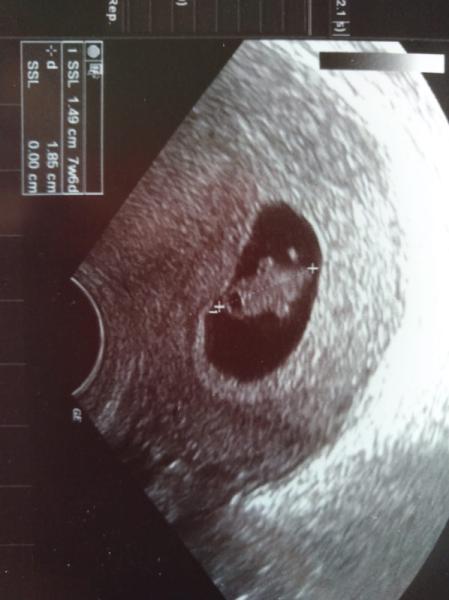

Hallo ihr Lieben, Mein Mann und ich waren heute beim Frauenarzt und es sieht alles gut aus mit unserem Minimi (unten auch ein Bild angehängt) Das Herz schlägt kräftig bei dem kleinen Gummibärchen und sonst sieht auch alles gut aus. In 4 Wochen ist dann die Nackenfaltenmessung. Lasst ihr das machen bzw. macht ihr noch weitere zusätzliche Untersuchungen? ET ist übrigens der 22.04. (7+6) morgen beginnt also schon die 9 ssw, Wahnsinn wir die Zeig vergeht Liebe Grüße Emma

Bild zu Auch zurück vom FA - Forum für April - Mamis

Ohhh so ein tolles Bild. Hoffe auch das ich nächste Woche ein so schönes Bild habe. Bin jetzt schon nervös, mir kann die Zeit bis zu 14 SSW nicht schnell genug vergehen